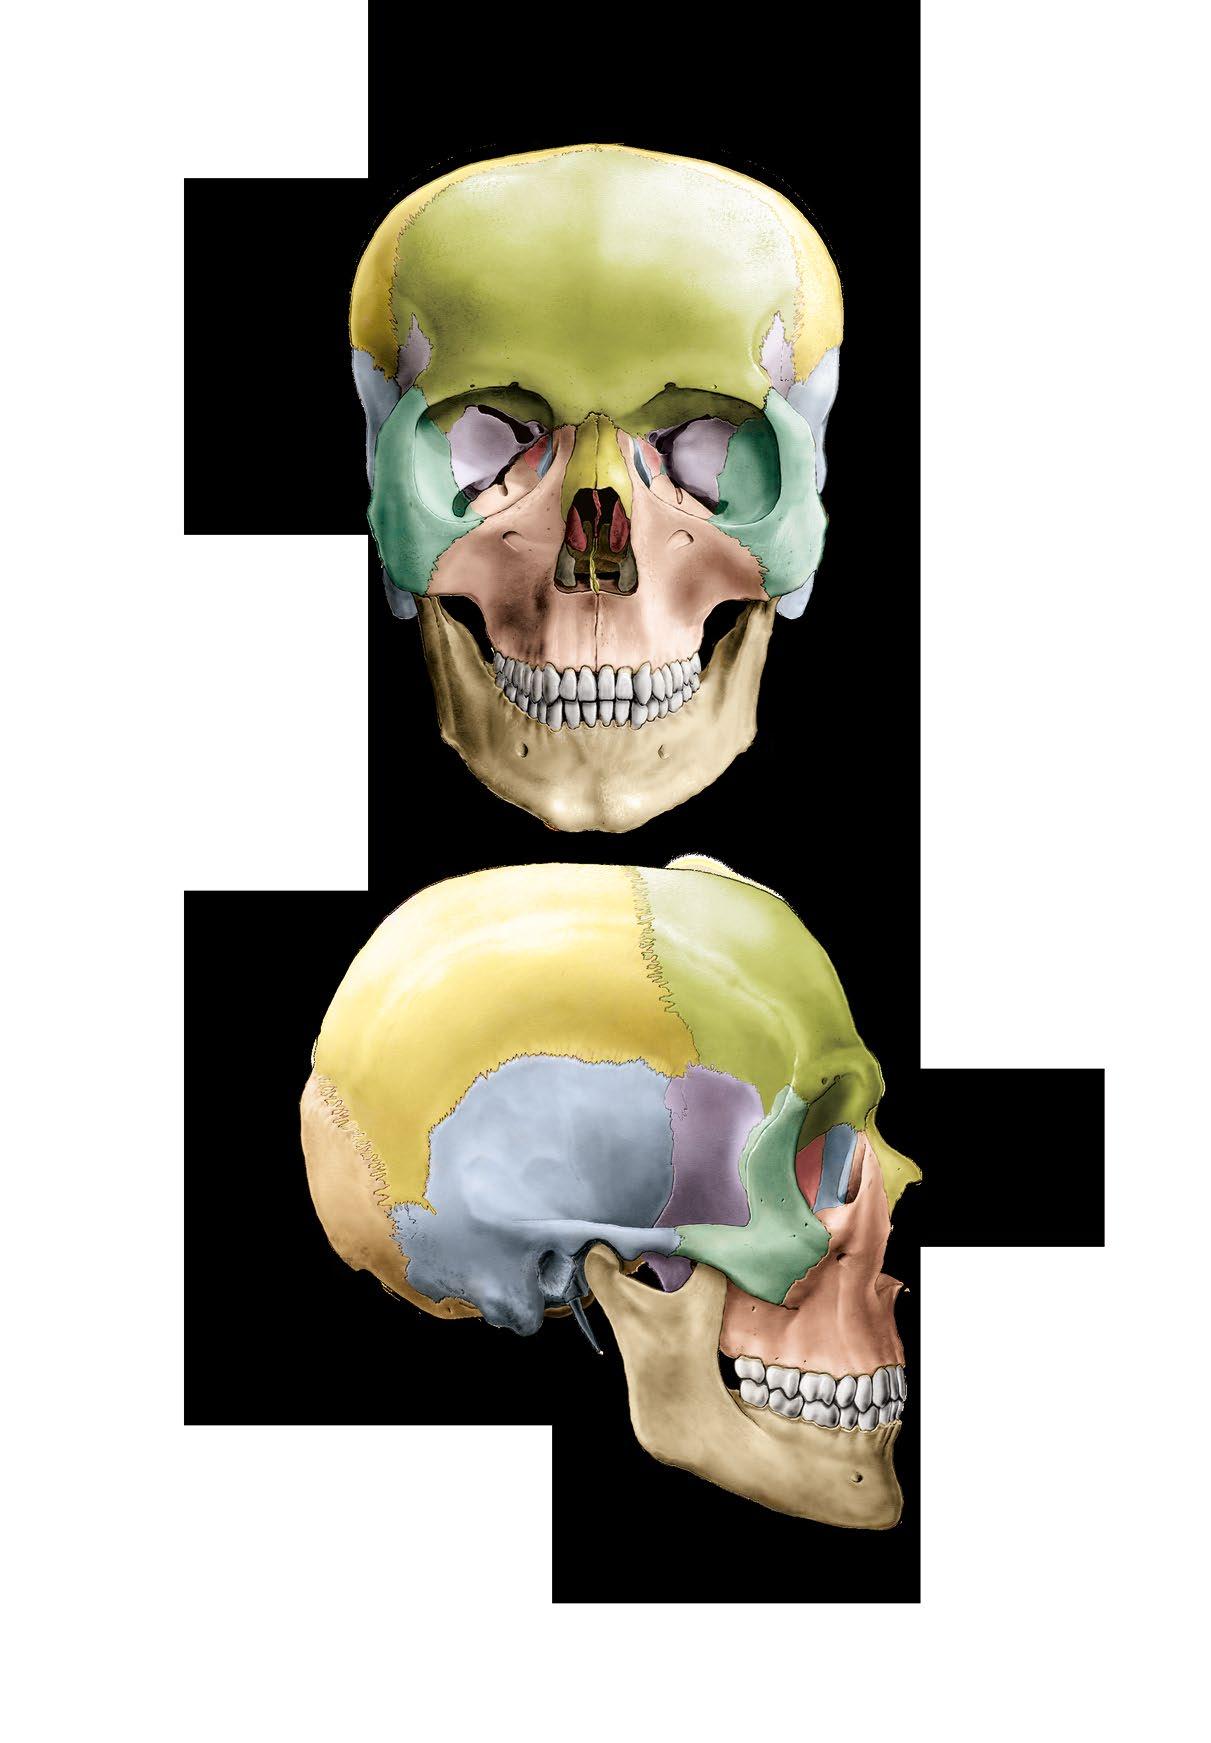

os parietale

os sphenoidale

os lacrimale os nasale vomer

os occipitale os temporale

Ossa cranii, kosti lebky

a pohled zpředu

b pohled zboku

Bones of the skull

a frontal view

b lateral view

os frontale os temporale os zygomaticum os ethmoidale, concha nasalis media

concha nasalis inferior mandibula

os frontale

os ethmoidale os ethmoidale os lacrimale os nasale os zygomaticum

os temporale

os zygomaticum

os occipitale

praemaxilla

maxilla os palatinum